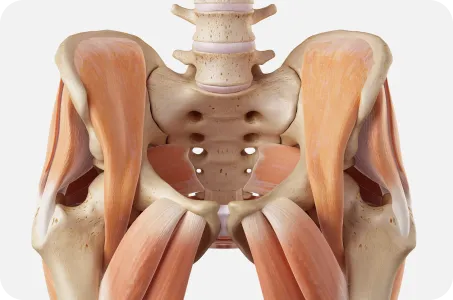

골반은 보행시 지면에서 올라온 충격을 척추로 전달하고

상체의 무게를 고관절과 하지로 전달하는 역할을 하기 때문에

힘전달의 중심축의 역할을 합니다.

골반이 틀어지면 척추와 어깨, 고관절, 무릎이 같이 틀어집니다.

골반은 허리와 다리를 연결하는 상하체 균형의 핵심 역할을 합니다.

우리의 몸은 한 곳이 틀어지면 연결되어있는 다른 곳도 틀어질 수 있습니다.

따라서 거북목, 일자목, 굽은등, 허리뼈의 틀어짐은 골반부터 교정해야 진도가 나갈 수 있습니다.